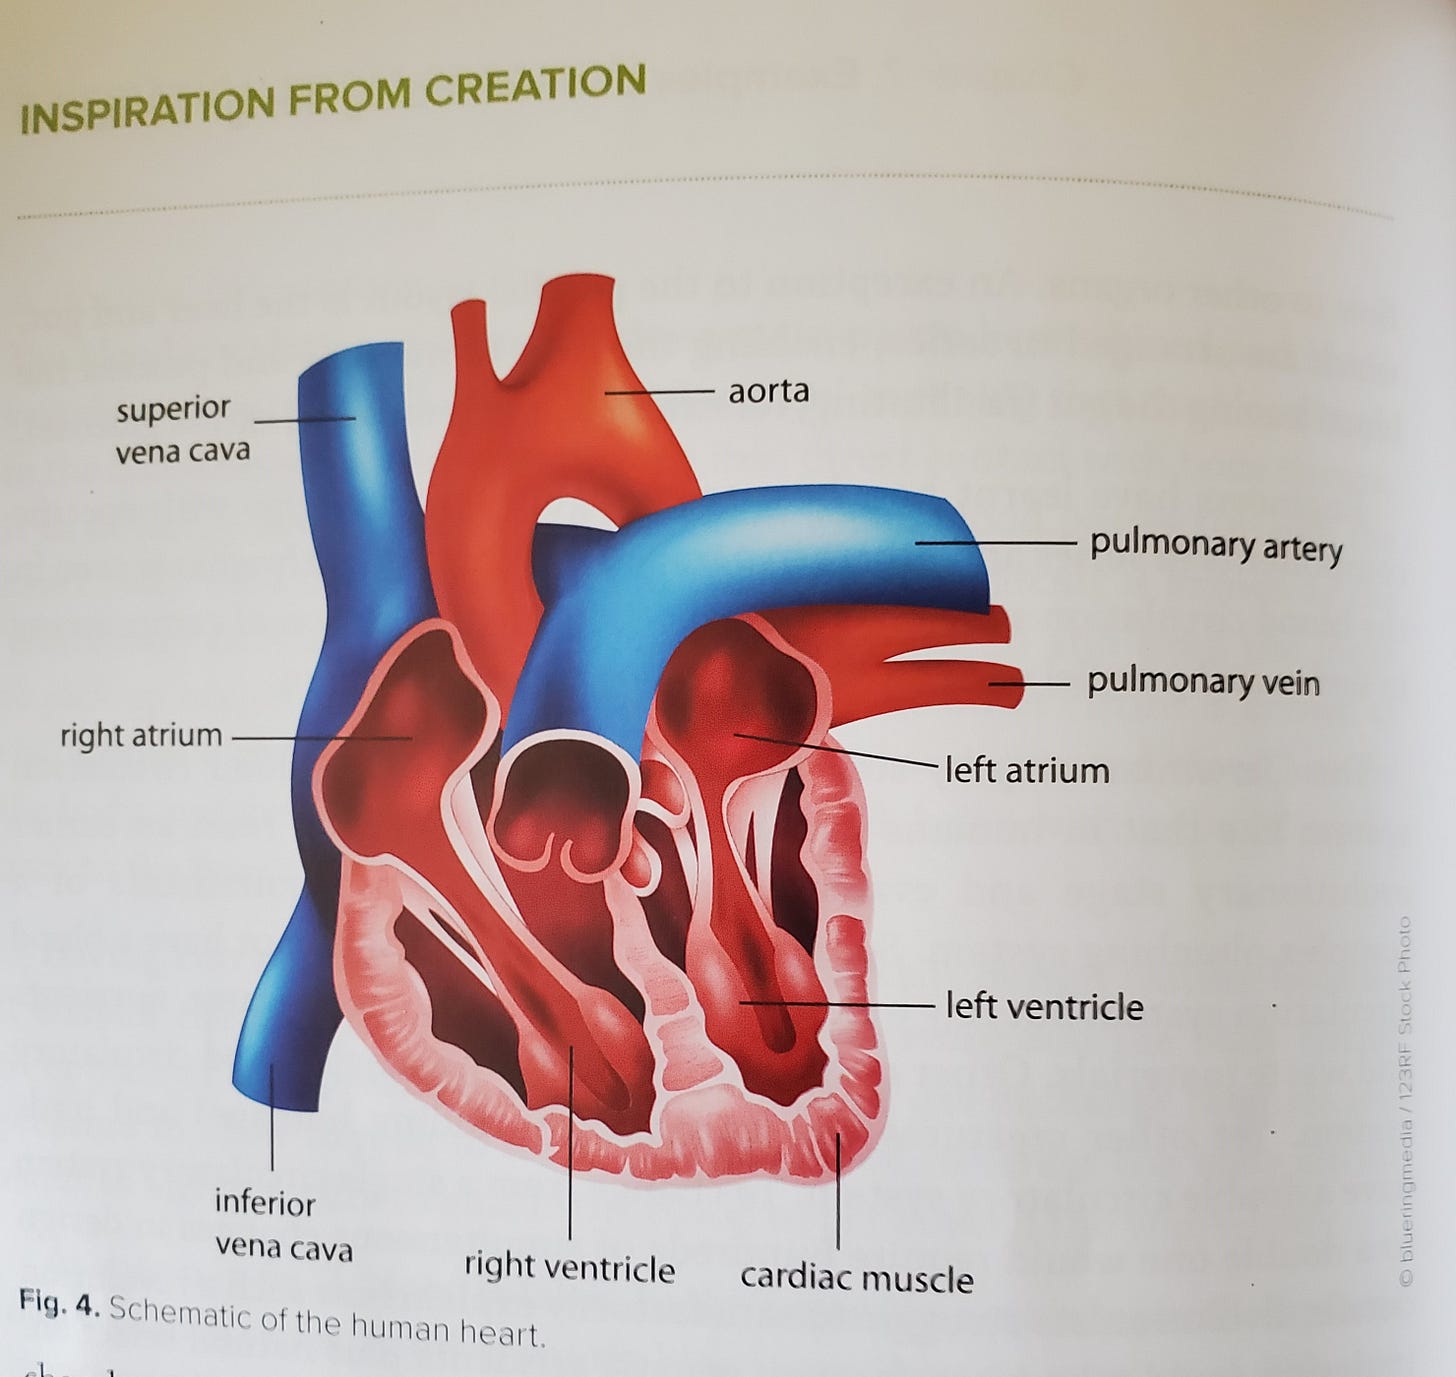

Consider the circulatory system. How does your heart know when it needs to speed up? How do your blood vessels know when to contract or expand? You can spend a lifetime just studying the human body and barely tap the depths of wonders.

Watch another class from “SciencewithSusanna”, on heart structure. https://www.sciencewithsusanna.com/cardiovascular-system